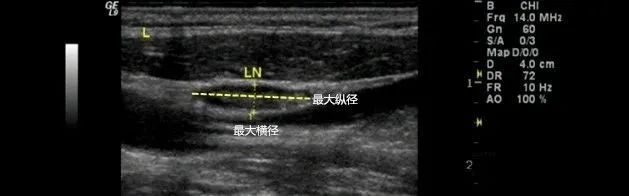

第二步测量淋巴结的大小并计算纵横比(L/T),就是指淋巴结最大纵径与最大横径的比值, 正常淋巴结的纵横比≥2 ;接下来就是观察淋巴结门, 正常淋巴结门位置居中、轮廓规整 ;还要注意 正常淋巴结皮髓质的分界清晰,皮质厚度小于淋巴门直径的1/2 ;

图2 淋巴结最大纵径与最大横径